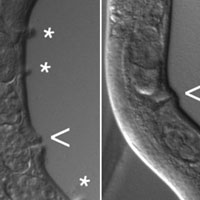

Эксперименты подтвердили, что микобактерии генерируют фенотипическое разнообразие в процессе деления. Когда равномерно флуоресцирующая родительская клетка делится, одна из ее дочек вскоре начинает флуоресцировать сильнее, чем другая. В большинстве случаев ярче флуоресцирует та дочка, которой достался «молодой» полюс материнской клетки (рис. 2, a, b). Это значит, что дочки различаются либо по активности эстераз, либо по проницаемости мембраны и клеточной стенки, и эти различия как-то связаны с возрастом клеточных полюсов.

Затем исследователи проверили, коррелирует ли сила флуоресценции с устойчивостью к антибиотику рифампицину, которым лечат туберкулез. Пронаблюдав за судьбой 96 индивидуальных клеток, которые сначала окрашивали кальцеином-АМ, а потом подвергали действию антибиотика, авторы обнаружили, что такая корреляция действительно существует: рифампицин сильнее действует на те клетки, которые ярче флуоресцируют, то есть накапливают больше кальцеина (рис. 2, c, d).

Рис. 2. Окрашивание кальцеином позволяет выявить изменчивость клеток по устойчивости к антибиотику рифампицину. a — изменчивость клеток по силе флуоресценции после окрашивания кальцеином. По горизонтальной оси — сила флуоресценции, по вертикальной — количество клеток. Размах изменчивости очень велик по сравнению с тем, что обычно наблюдается у других бактерий. b — график, показывающий, что из двух сестринских клеток сильнее, как правило, флуоресцирует та, которая унаследовала от родительской клетки ее «молодой» конец. По горизонтальной оси — отношение силы флуоресценции дочерней клетки, которой достался молодой полюс матери, к силе флуоресценции ее сестры, которой достался старый полюс. с — схема эксперимента по выявлению связи между силой флуоресценции и устойчивостью к рифампицину. d — график, показывающий, что рифампицин сильнее действует на клетки, которые ярче флуоресцируют, то есть накопили больше кальцеина. По горизонтальной оси — сила флуоресценции, по вертикальной — суммарное число потомков, произведенных клеткой за 6 часов жизни в среде с рифампицином и последующие 12 часов жизни в обычной питательной среде. Рисунок из обсуждаемой статьи в Nature